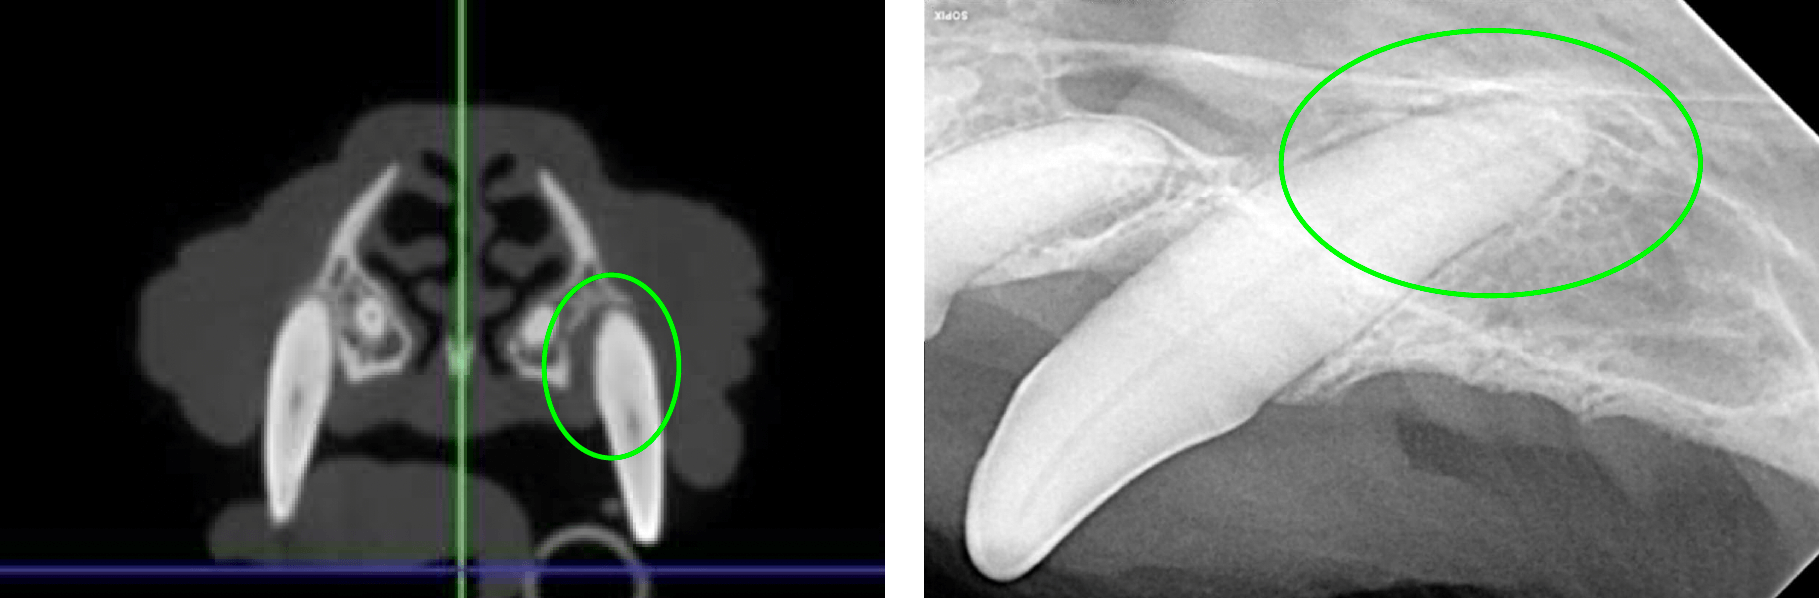

Below: Bone loss affecting upper left canine tooth

Below: Imaging of both sides of the lower right 4th premolar

Furcation exposure level 2 indicating bone loss under the crown